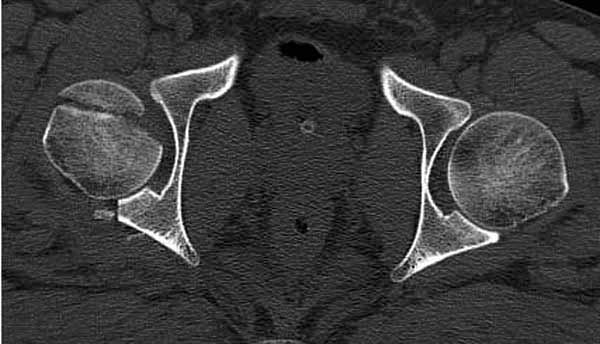

Имя     : 2 Fem head  CT.jpg

Тип     : image/jpg

Размер  : 42793 байтов

Описание: отсутствует

Url     : http://weborto.net:8080/pipermail/ortho/attachments/20111231/d311d17a/attachment-0011.jpg